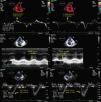

other parameters for characterization of RV morphology and function: in apical 4-chamber view, diastolic RV diameters (Figure 1) and the gradient between the right ventricle and right atrium in systole (RV/RA gradient). In parasternal short-axis (at the level of the papillary muscles): left ventricular diastolic diameters, to calculate the diastolic left ventricular eccentricity index (LVEI) (Figure 3).

Figure 3.Echocardiographic measurements in a pulmonary hypertension patient at rest (left) and at peak exercise (right); top – diastolic left ventricular eccentricity index; bottom – RV/RA gradient. D1 and D2: left ventricular diameters; LV exc index: diastolic left ventricular eccentricity index; RV/RA grad: right ventricular/right atrial gradient in systole.